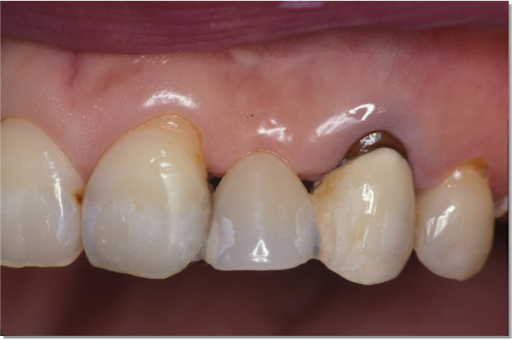

下顎臼歯部が欠損した患者さんのインプラント治療の症例②(うえだ歯科)

上田大介(うえだ歯科)

症例詳細

| 主訴 | 全顎治療希望、下の奥の歯が無いので全く噛めない。綺麗で噛めるようになりたい |

| 治療内容 | 下顎臼歯部欠損放置のため、臼歯部においてスペースがないため、全顎治療を行い咬合再構成を行う。 早期においてインプラント治療、咬合関係を模索した後、全顎にわたりセラミックによる補綴治療、その後メインテナンスに移行 |

| 治療費 | 5,410,000円(税込)(インプラントすべて含む) |

| 治療期間 | 1年8ヶ月 |

| 治療回数 | 80回 |

| 想定されたリスク | 食いしばり(パラファンクション)によるセラミックの破折、歯の破折 |